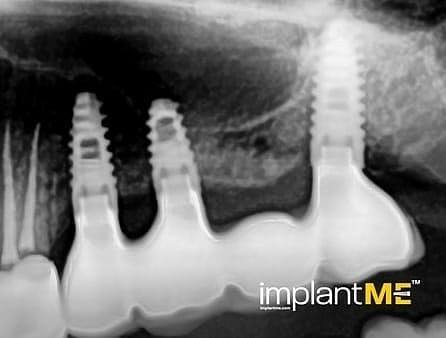

Атрактивните и особено здравите заби не се само одлучувачки дел од нашиот изглед, туку и на нашата личност. Во минатото, губењето на еден или повеќе заби имаше одлучувачка улога врз изгледот на луѓето. Поради модерната орална имплантологија, ова повеќе не е случај. Со релативно мали процедури за орална хирургија, индивидуалните или сите непостоечки заби можат да бидат заменети со импланти, естетски и функционално еднакви на природните заби. Преку вметнување импланти во форма на корен, можно е да се избегнат промени на соседните заби и да се зацврстат коронки што тешко може да се разликуваат од вистински заби во празнините на забите. Коронките или мостовите поддржани од импланти се прицврстени на колец зацврстен во коска, што им дава на пациентите џвакање со чувство скоро нималку различно од нивните заби. Во случај на потполна беззабост, имплантите може да претставуваат сигурна потпора за мобилна протеза, како и за големи фиксни мостови.

Забната протетика поддржана од имплант тесно се доближува до природните заби. Коронките водат со нивниот природен изглед, имплантите со нивната стабилност, а двете заедно со нивното позитивно влијание врз функционалното зачувување на целиот мастикаторен апарат.